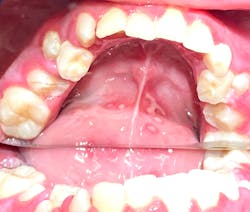

Note: The pictures are not of the highest quality as the patient was in extreme discomfort when I took them.

Definitive diagnosis is likely one of two: Herpangina or acute primary herpetic gingivostomatitis

The saying “nothing is for certain unless it’s in a petri dish” stands true in all pathology cases, including this one. However, based on the symptoms and clinical presentation, I was able to surmise that it was more than likely either herpangina or APHG, although I’m leaning toward APHG.